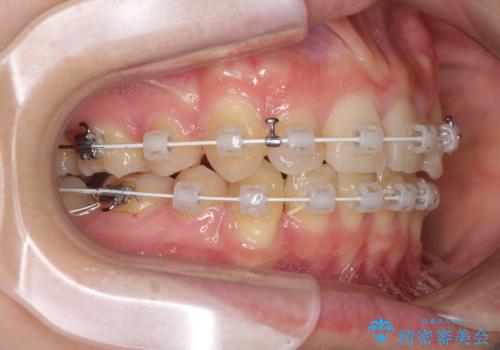

気になる八重歯を治したい ワイヤー装置での抜歯矯正

- 上下の八重歯や乱杭歯を気にして来院され患者様です。

スペースを確保するため、上下左右の第一小臼歯を抜歯し、ワイヤー装置に矯正することとしました。

結婚式の予定があったため、まずは前歯をきれいに整えるようにしました。

結婚式の時には一時的に前歯の装置を外し、口元を気にせず笑える結婚式を迎えることができました。

その後スペースを閉じるために時間を要しましたが、満足のいく仕上がりとなりました。